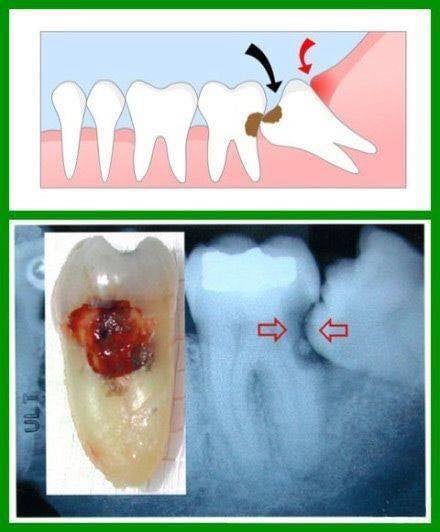

2.親知らずと隣の歯のあいだに汚れが溜まり、気付かぬうちに隣の歯がむし歯になって、最悪の場合、抜歯しなくてはいけないこともあります。

2.隣の歯がむし歯になっている。またはなる可能性がある。